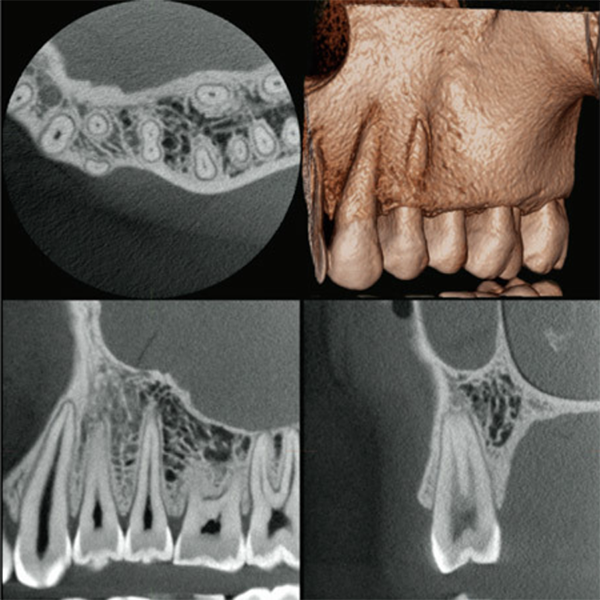

歯科用CT撮影システム

当院では診断のために「歯科用CT撮影システム」を利用しています。

思い通りの方向から3次元画像が撮影できるため、従来の2次元パノラマ画像では撮影できなかった異常を見つける事ができます。

従来の2次元パノラマ画像

3次元CT画像

3次元CT画像を自由に動かして、あらゆる方向から診断する事ができます